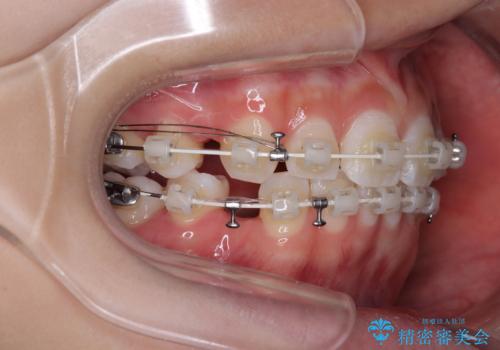

- 矯正装置

- 審美装置

- 2年

- 10-30回

下顎はデコボコが気になっていたため、上下左右第一小臼歯4本を抜去して、ワイヤー装置にて口元の突出感を改善するよう矯正治療を行うこととしました。